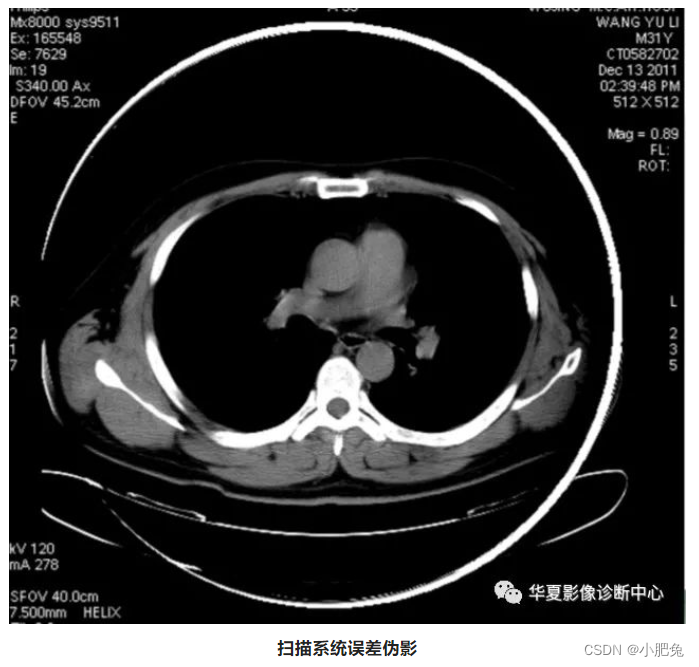

七、扫描系统误差伪影

在扫描期同,系统本身对不同的测量数据,根据每天的校正测量数据会及时的做出修正。如超出该修正范围,可出现错误信号甚至无信号,导致图像中的环状伪影,该伪影的半径对应于探测器阵列中出现测量误差探测器的位置所在。

扫描系统误差伪影

处理方法

系统误差的防止方法一般是每天开机或连续几小时不工作后,作系统校正测量及其定期地作系统维护。